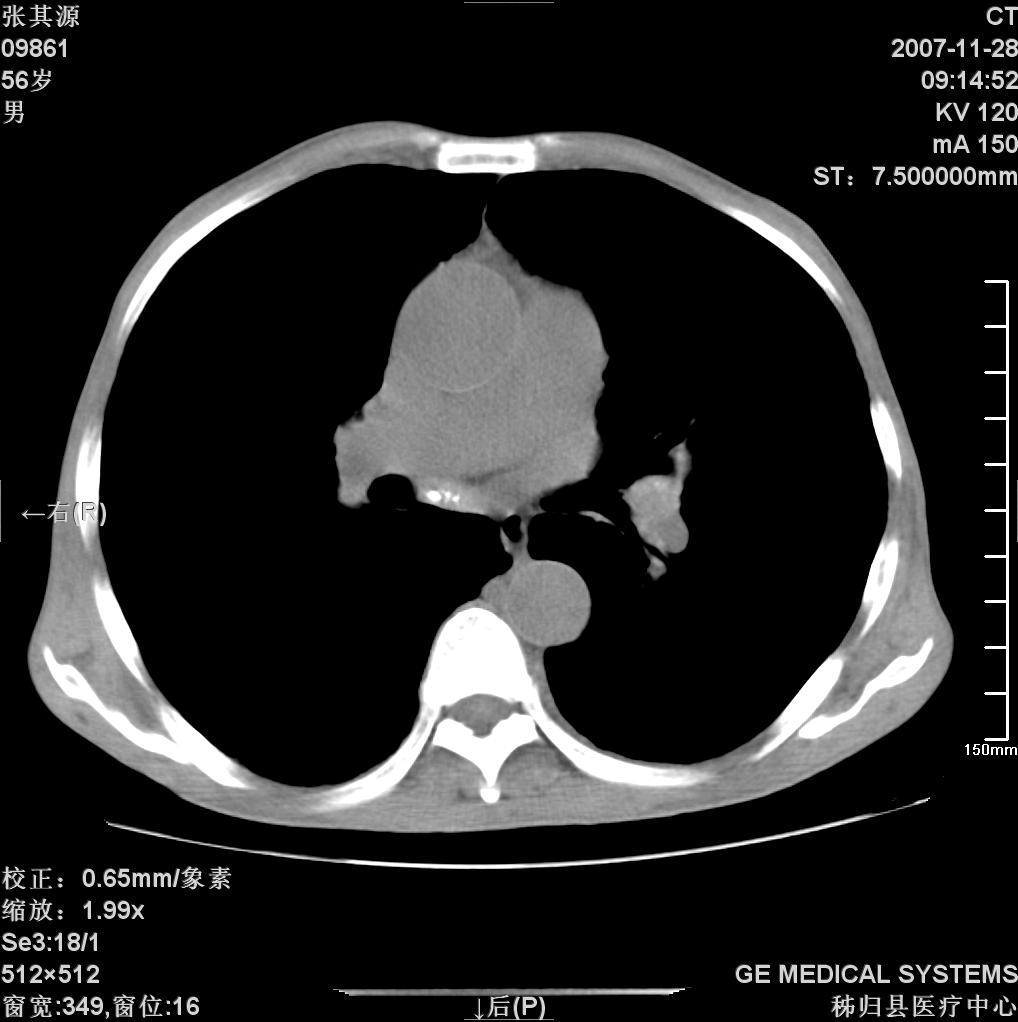

患者因阻塞性黄疸入院,发病前10天持续中等程度发烧.术前检查发现两肺弥漫性病变,请各位大虾会诊,除了考虑急性血源性肺结核外,还有其他什么疾病可能.

补充一下,该患者没有与尘肺相关职业史。请大家帮忙会诊一下,外科医生打算为其做胆总管肿瘤做手术的,现在在等我们的结果。谢谢各位了。

双肺多发粟粒样病灶,右肺胸膜下结节样病灶,气管前腔静脉后及隆突下均见肿大淋巴结,结合胆道肿瘤病史首先考虑转移。另外心影密度略低,时间格显示,是否有贫血?查明白再手术吧!